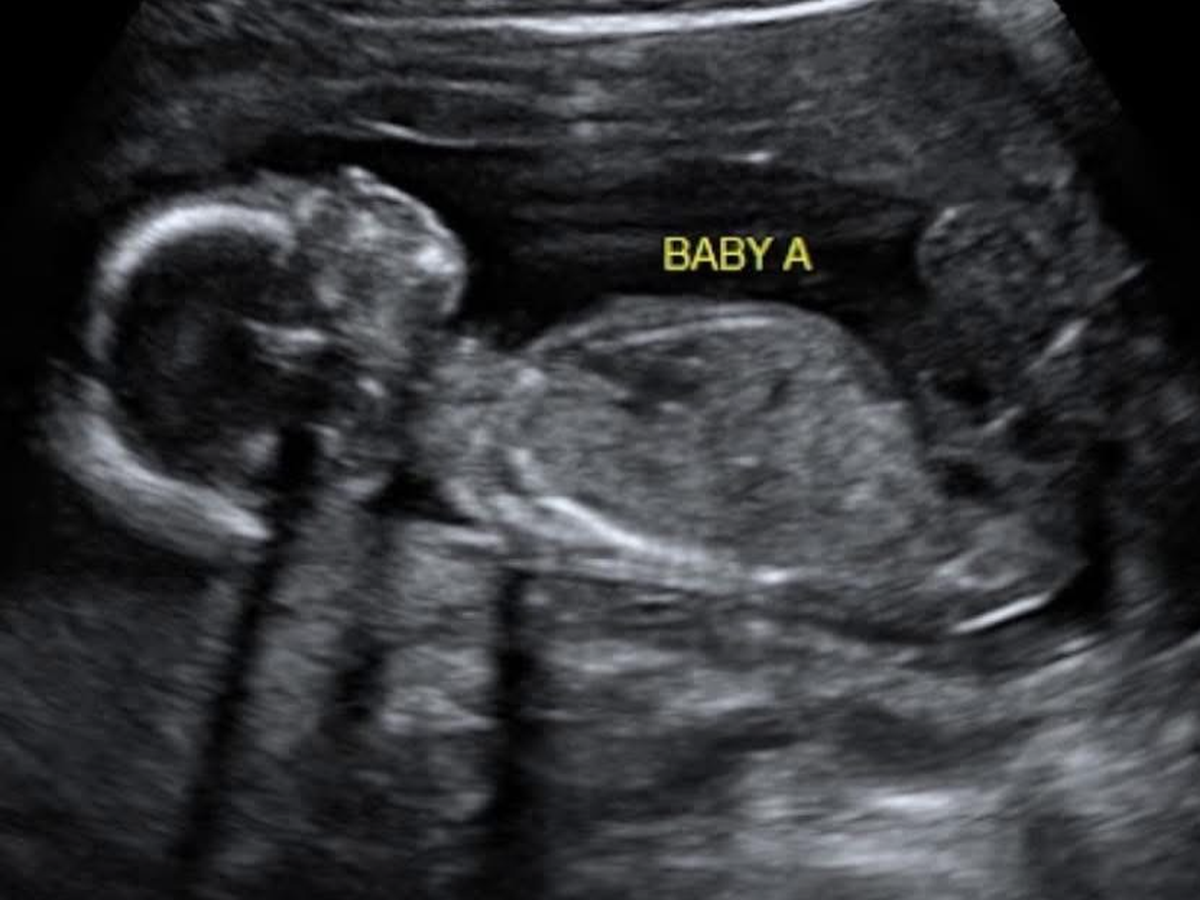

My name is Cindy Arnold and my daughter and son in law, Kara and Perry Stevens, are expecting our first grandbabies....TWINS! One boy, Walt, and one girl, Lumi.

On Monday, March 31st, Kara and Perry went to the doctor for a routine anatomy scan ultrasound at 21 weeks. Everything looked great with Walt and Lumi until the tech got to Walt’s heart. Unfortunately, only the right side of Walt’s heart developed in the womb, and he’s been diagnosed with HLHS. This is a rare but very serious heart defect that would result in death shortly after birth without a series of surgeries. What was once going to be a natural home birth is now going to involve Kara moving to Durham, NC five weeks before her due date to prepare to give birth to Walt and Lumi at Duke, where Walt will be surrounded by some of the top pediatric cardiologists and children’s surgeons in the country. The tentative plan is for him to have his first surgery 5-10 days after birth, his second surgery at 4 months old, and his third around 4 years old. He will likely still need a heart transplant around 20-30 years old.